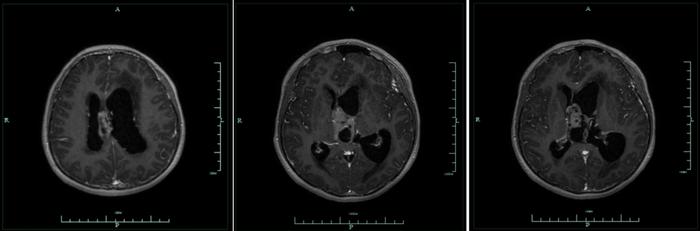

17岁少年小陈(化名)近日经历了惊心动魄的生命转折。这个本该在校园挥洒青春的少年,却因每日30余次排尿、单日排尿量高达18000毫升,伴随持续头痛、视力骤降,被父母紧急送往咸宁市中心医院。经神经外科李明昌教授团队检查,发现其第三脑室深处潜藏着直径达4.5厘米的巨大肿瘤,犹如一颗"深水炸弹"压迫脑组织,已引发严重脑积水。

△术前MRI

△术前MRI该病例堪称神经外科领域的

解剖险境:肿瘤盘踞大脑核心区,毗邻下丘脑、视神经等重要结构

功能禁区:传统开颅手术极易损伤记忆、内分泌等关键神经功能

技术壁垒:深部操作面临视野受限、止血困难等难题

放射科通过DTI纤维束成像技术,精确显示了肿瘤与周围神经纤维束、血管的三维关系;肿瘤科评估了可能的病理类型及后续治疗方案;病理科和输血科做好了充分的术中快速病检和输血准备;麻醉科制定了详细的术中生命体征监测方案。